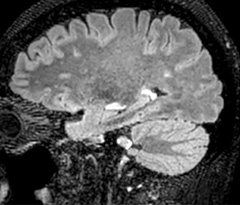

A two year follow-up scan of a CPA meningioma using both Ingenia 3.0T without CS and Ingenia Elition 3.0T with Compressed SENSE allows for a nice comparison to demonstrate the protocol improvements achieved on the Elition: 3D FLAIR has a shortened scan time, improved SNR and still the same spatial resolution. BrainView (3D T1 TSE) has improved spatial resolution and SNR with shortened scan time. For 3D T2 Drive the spatial resolution has been improved. 3D THRIVE used to have an interpolated 0.8 mm slice thickness, but true thickness at 1.6 mm, so that axial slices displayed a decent quality, but reformats were suboptimal.

Compressed SENSE is used on Elition to improve spatial resolution and reduce the non-interpolated slice thickness to allow smoothly reformatted images. Total scan time (adding SmartBrain and an additional b2000 diffusion) was 13:19 on Ingenia, and is now reduced to 10:42 on Ingenia Elition.

Ingenia 3.0T (without Compressed SENSE)

3D FLAIR (without Compressed SENSE)

3D FLAIR

1.0 x 1.0 x 1.0 mm*

4:24 min.

3D TSE T1w (without Compressed SENSE)

3D TSE T1w

1.0 x 1.0 x 1.2 mm*

2:40 min.

Ingenia Elition 3.0T with Compressed SENSE

3D FLAIR (with Compressed SENSE)

2:50 min.

3D TSE T1w (with Compressed SENSE)

2:10 min.

*true voxel size, without interpolation